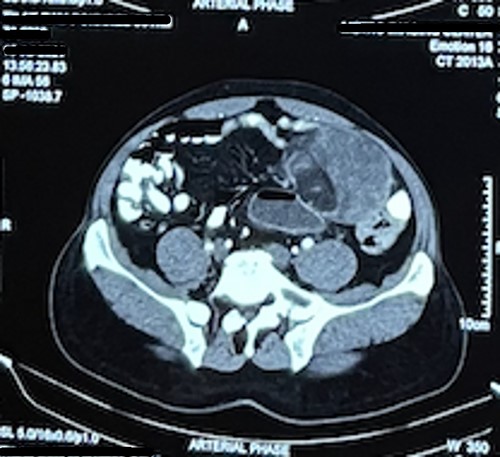

Laboratory test including tumor marker (carcinoembryonic antigen) was normal. Abdominal ultrasonography revealed heteroechoic mass over left iliac fossa with regular borders. Computed tomography (CT) of the abdomen revealed well-defined space-occupying lesion of size 10 × 8.5 × 7 cm at the left iliac fossa. There were no areas of calcification; however, plane between the mass and the bowel was lost in few places suggesting of invasion (Figs 1 and 2).

Mesenteric liposarcomas is common among males of 50 and 70 years. It is locally aggressive, non-metastasizing and presents as a deep-seated mass along the root of mesentery. It can grow into a large-sized mass [4]. Patients present with nonspecific symptoms of pain in abdomen, lump in abdomen, abdominal distention and weight loss early satiety [6, 7]. CT helps in determining the size, characteristic and invasion to adjacent organs. CT images shows well-defined to poor margination, invasion, contrast enhancement, inhomogeneity and CT numbers greater than normal fat [8].